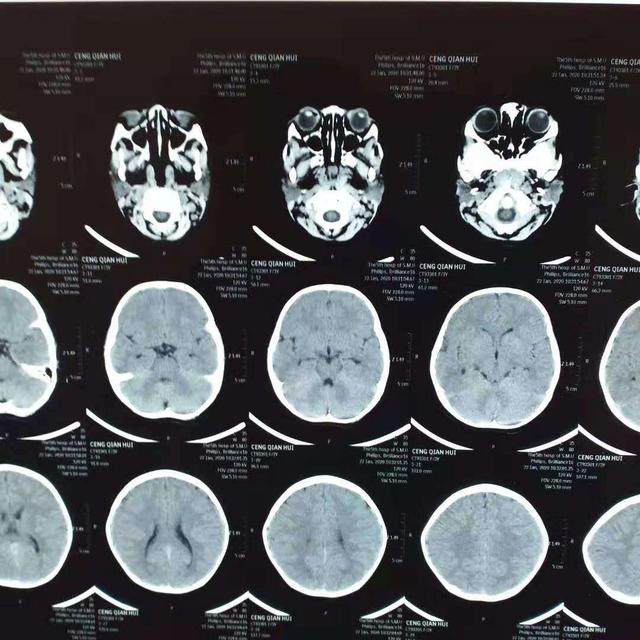

治疗后照片

3岁小孩,玩耍时跌倒头枕部着地受伤,致头疼不适,送去某医院求治,CT检查发现:左枕及小脑硬膜外血肿(图1-2)。该医院医生意见:开颅手术清除血肿。理论上讲,确实有手术指征!但是这个病人家属担心开颅手术风险太大,对小孩影响不好,拒绝手术。后来经过中西医结合保守治疗(20天左右),逐渐好转并完全治愈(图3-4)。有时候病人的治疗需要根据病情综合考虑,如果没有慎重考虑,匆忙做了手术,可能符合治疗原则,但是给病人带来了不必要的痛苦,增加了病人的经济负担和心理创伤!当然这更需要医生的诊疗技术、责任心和担当![加油][加油][加油]